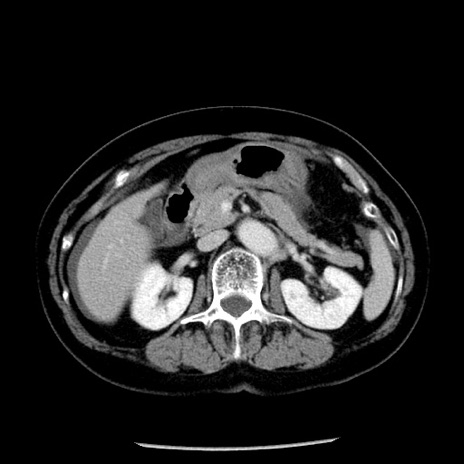

症例13(横断像)

【症例】70歳代女性

【主訴】腹痛、嘔吐

【現病歴】15時間程前(昨晩)より腹痛あり。今朝になっても症状の改善なく、嘔吐あり。腹痛も増悪あり、救急外来受診。

【既往歴】子宮癌全摘術後

【身体所見】意識清明、BP 121/72mmHg、P 74bpm、SpO2 100%(RA)、腹部:平坦・軟、腸雑音ほぼ聴取せず。下腹部・心窩部・臍左上に圧痛あり。反跳痛なし。

【データ】WBC 10600、CRP 0.15